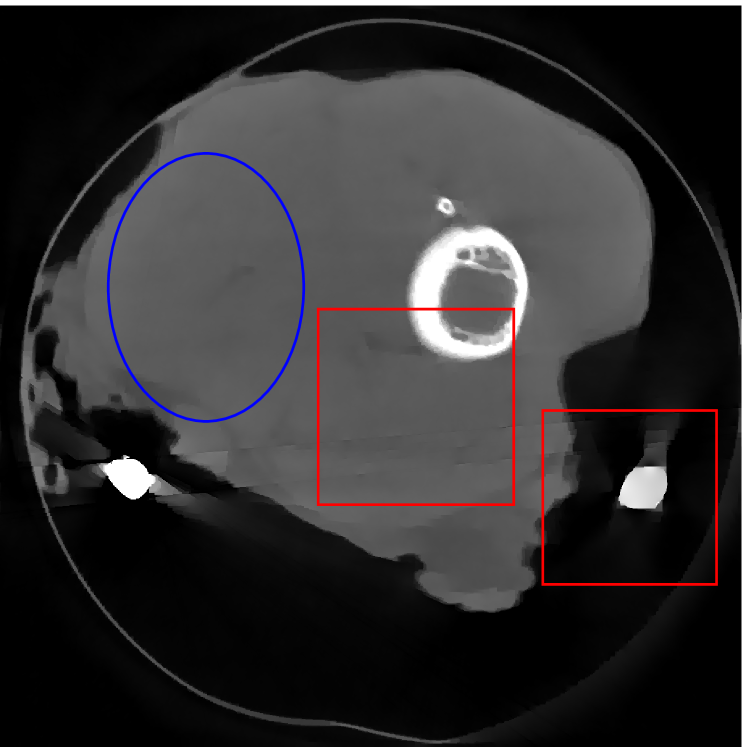

4.2 Numerical experiments: real data

We perform a CT scan of a chicken leg placed in a disposable cup (Figure 10(a)). We first scan the chicken leg without metals (Figure 10(b)) to create a reference image using FBP algorithm. Then, we place two steel thread nails on each side of the chicken leg and scan the subject again using the same scanning protocol (Figure 10(c)). The projection data is acquired from a MicroCT scanner equipped at the Division of Nuclear Technology and Applications, Institute of High Energy Physics, Chinese Academy of Sciences. The X-ray source is with 90 kV and 70 mA energy and the flat plane detector contains pixels. The scanning trajectory is a full circle with equally spaced views at per view. The physical size of each detector unit is . The distance from the X-ray source to the detector is . In order to conduct a 2D experiment, we choose the 512th row of the detector array.

Figure 11 shows the images reconstructed using FBP, the analysis model (2.12), the inpainting model (2.13) and the segmented image from the image obtained by (2.14). The reference image without metal implants are shown in Figure 11(a). All the images in this subsection are displayed within the grayscale interval . The segmented image shown in Figure 11(e) is used to estimate the weights needed in NMAR and the re-weighted JSR model.

Figure 12 shows a comparison between the reconstructed image from NMAR and the unweighted JSR model. Figure 13 shows a comparison between the reconstructed images from TV-FADM and the proposed re-weighted JSR model. Zoom-in views are provided in both Figure 12 and Figure 13 for a better visual assessment. As one can see that the reconstructed images from the unweighted JSR model and TV-FADM are less noisy than NMAR as indicated by the blue ellipse curve, whereas NMAR does a better job in preserving image features and suppressing metal artifacts. However, there are also new artifacts around the metal on the right as shown in Figure 12(d). The proposed re-weighted JSR model has best overall performance in terms of feature preservation, noise and metal artifact reduction.